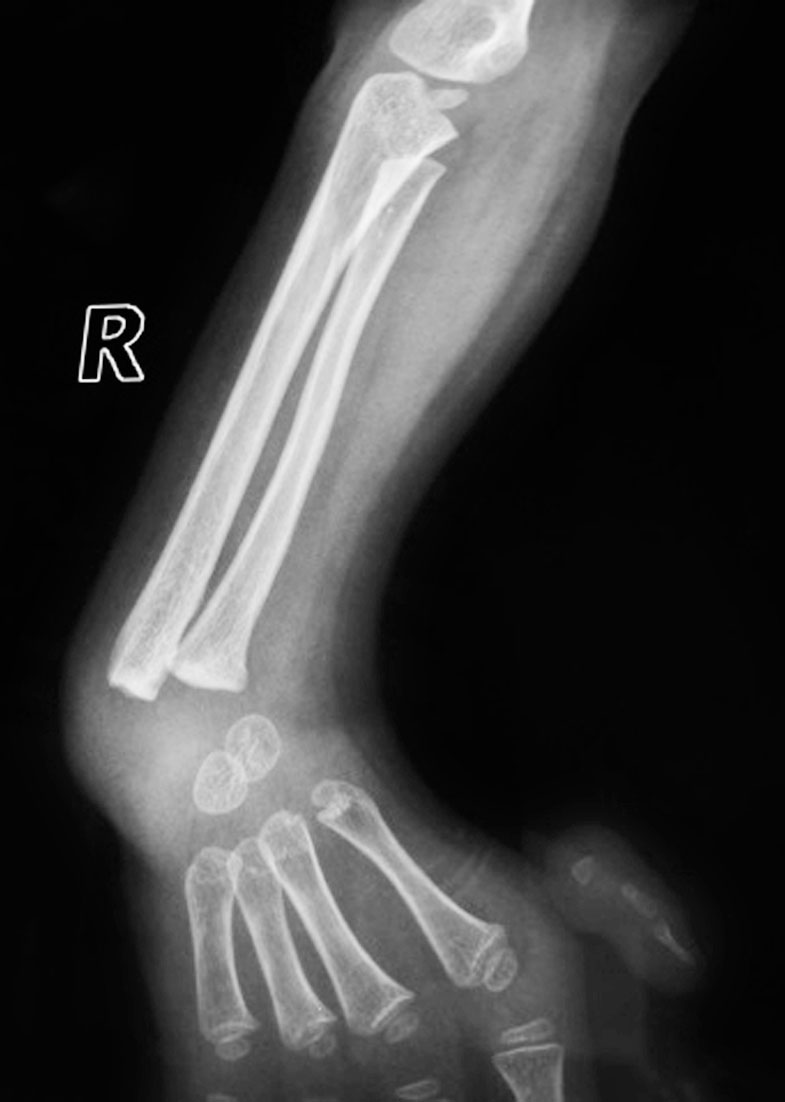

图1-2-23 右前臂桡、尺骨全长融合